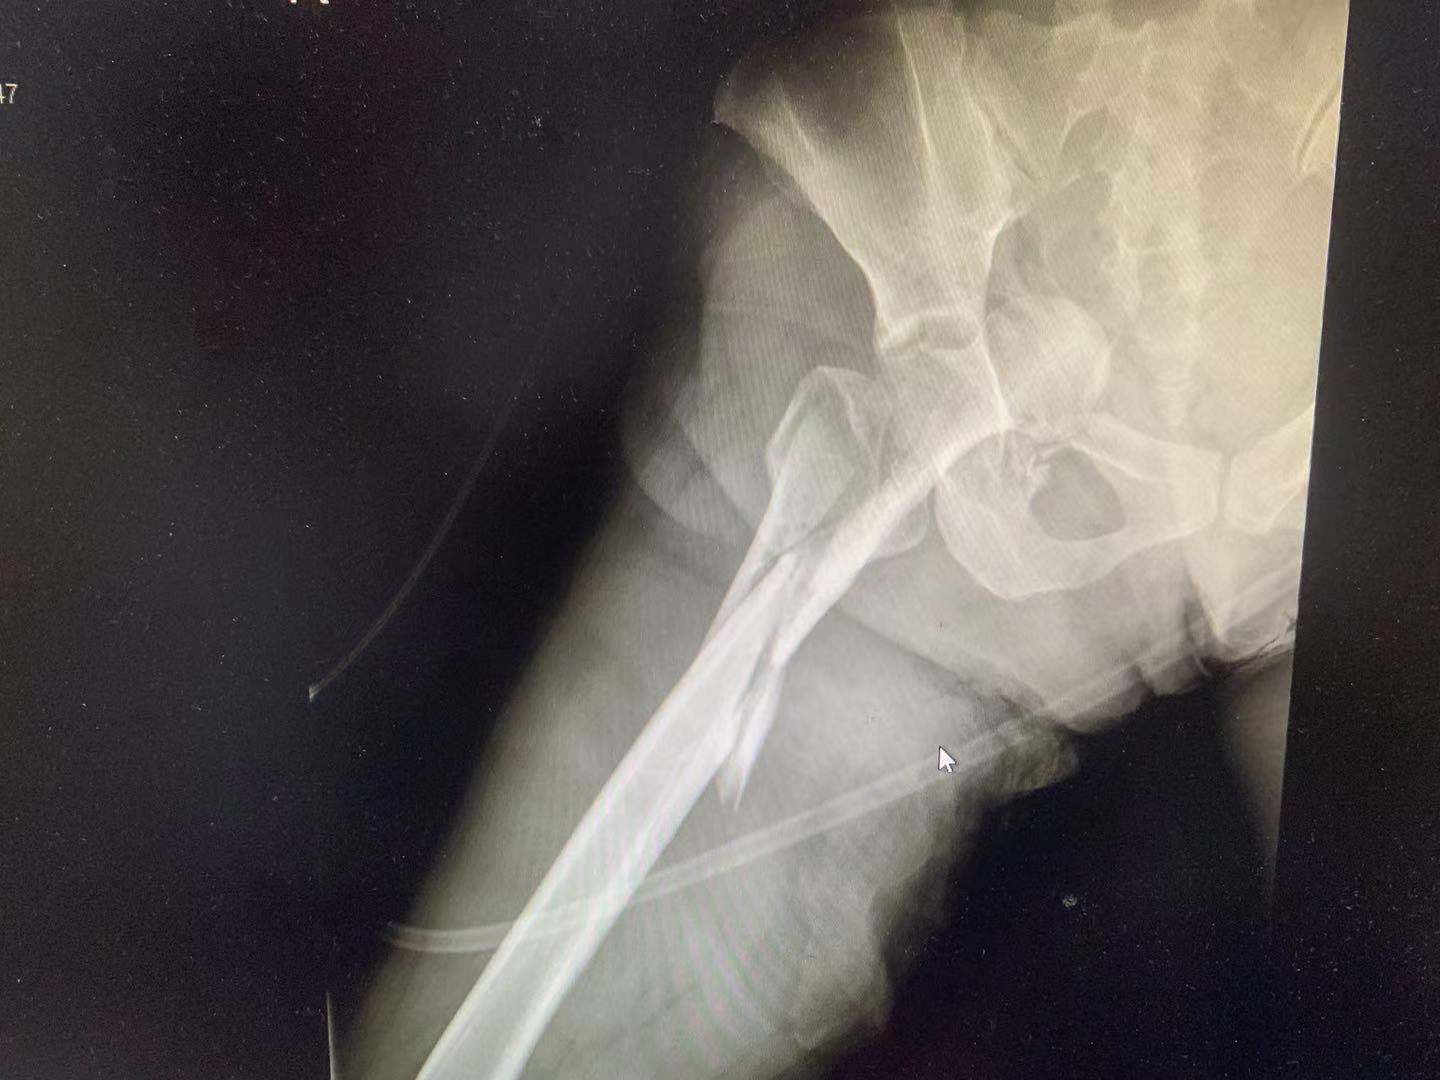

据宁波市第一医院创伤中心的接诊医生介绍,当时患者呈昏迷状态,瞳孔对光反射已经比较迟钝了,血压很低,右髋部畸形。创伤中心的值班医生迅速启动了危重创伤患者抢救预案,开通多通道静脉输血补液,并使用了骨髓穿刺补液技术快速补充血容量。快速检查诊断,患者诊断为失血性休克,全身多处骨折,右侧髋臼中心性脱位,并伴随腹部巨大肿瘤并出血。

考虑到患者骨盆髋臼骨折出血量大,在大量输血补液纠正失血性休克的基础下,12月13日当天,血管外科急诊对其进行了第一次手术,术后送ICU继续抢救。

一个星期后,患者的血色素初步稳定,但是仍有缓慢下降,同时患者还出现了严重的肺部感染等并发症,如果还是不能解决髋臼骨折脱位情况,患者极大可能因出现各种并发症而导致生命危险。经全院总会诊讨论后,决定把握住这稍纵即逝的手术时机。12月23日,患者进行了第三次手术,手术由宋庆华副主任医师主刀。这次手术非常顺利,术后患者并发症得到了有效控制,病情也一天比一天好,生命体征也越来越稳定了。

2021年1月2日,宁波市第一医院的修复重建外科对患者进行了第四次手术——左侧股骨近端骨折手术。“目前欣然的病情恢复得非常好,已经远远超出了我们的预期,这种严重创伤患者能救活就已经是奇迹了,下一步就是如何解决腹部肿瘤的手术了。”主管医师说。